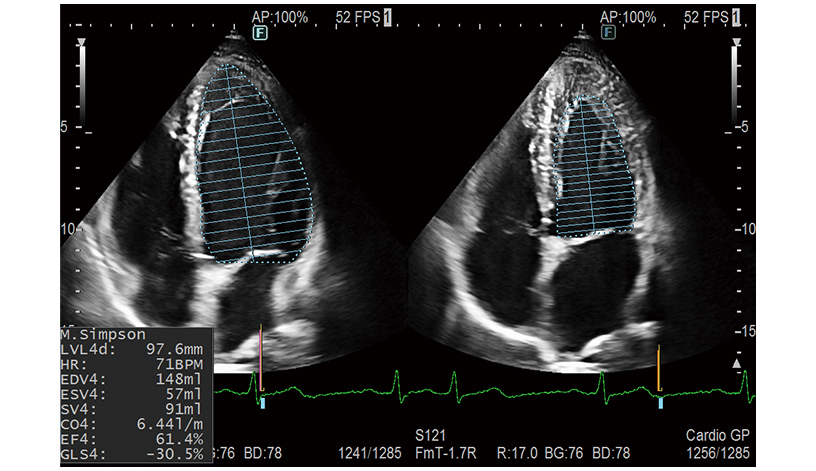

Kardiyak İşlevi

Yapay zeka teknolojisini kullanarak kardiyovasküler muayeneler için etkili olan otomatik ölçümleri destekler*1. Kullanıcılar muayeneleri sorunsuz ve etkili bir şekilde gerçekleştirebilir.

- Doppler İmleç Asistanı: Örnek geçidi konumunun otomatik ayarı

- LV, LA, RA Hacim otomatik ölçümü